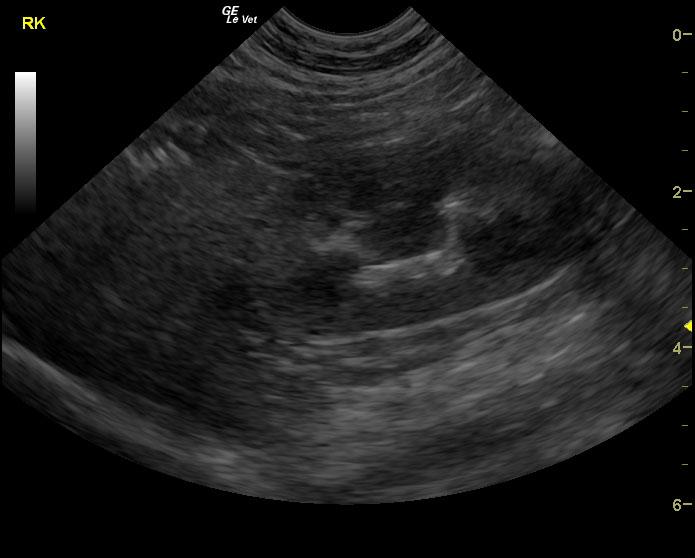

A 6-year-old SF DSH cat was presented for evaluation of chronic cystitis that was non-responsive to antibiotic and Adequan therapy. Both urinalysis and urine culture were within normal limits.

A 6-year-old SF DSH cat was presented for evaluation of chronic cystitis that was non-responsive to antibiotic and Adequan therapy. Both urinalysis and urine culture were within normal limits.